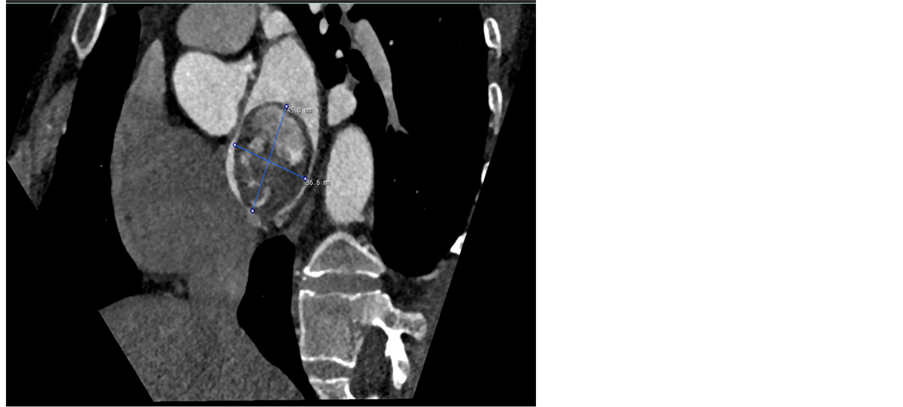

Transthoracic echocardiography revealed a tumour originating from the interatrial septum fossa ovalis in the left atrium (Figure 1). To determine the size and shape a CT-scan of the heart was conducted; the tumour measured 51 × 49 × 37 mm (Figure 2). Coronary angiography revealed abnormal arterial supply from RCA and CX to the tumour (Figure 3).

Figure 3. Anomalous vessel supply to the myxoma. Angiogram of the circumflex (left) and right coronary (right), demonstrating supply to the mass.

vessels supplying the tumour is most commonly CX followed by the RCA [6] , while a limited number of studies have demonstrated the rare condition with coexisting coronary artery supply as seen in our case [12] [13] [14] [15] [16] .